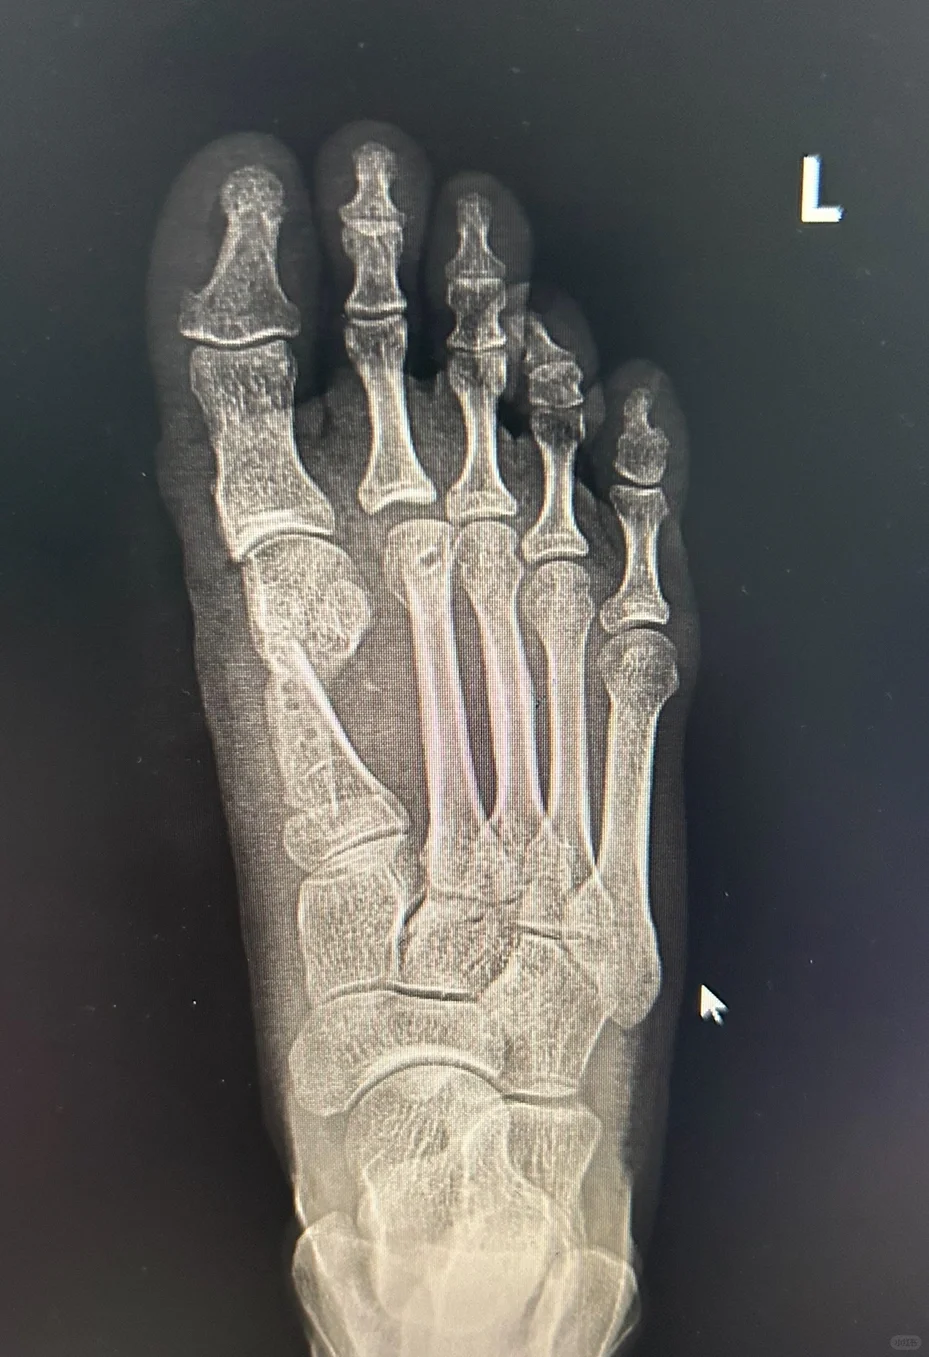

以前对于这种畸形的翻修都是原位断骨,哪来哪去的方法,两次在同一部位断骨,不仅血运损伤很重,拇趾会更短,而且断骨非常不稳定,很容易跑位置,不能在最佳的位置上稳定愈合。

经过多年研究,和大量微创术后患者的配合,我们成功研究出针对这种畸形的翻修方法。

可靠,接触面积大,术后可以下地负重。关节匹配良好。